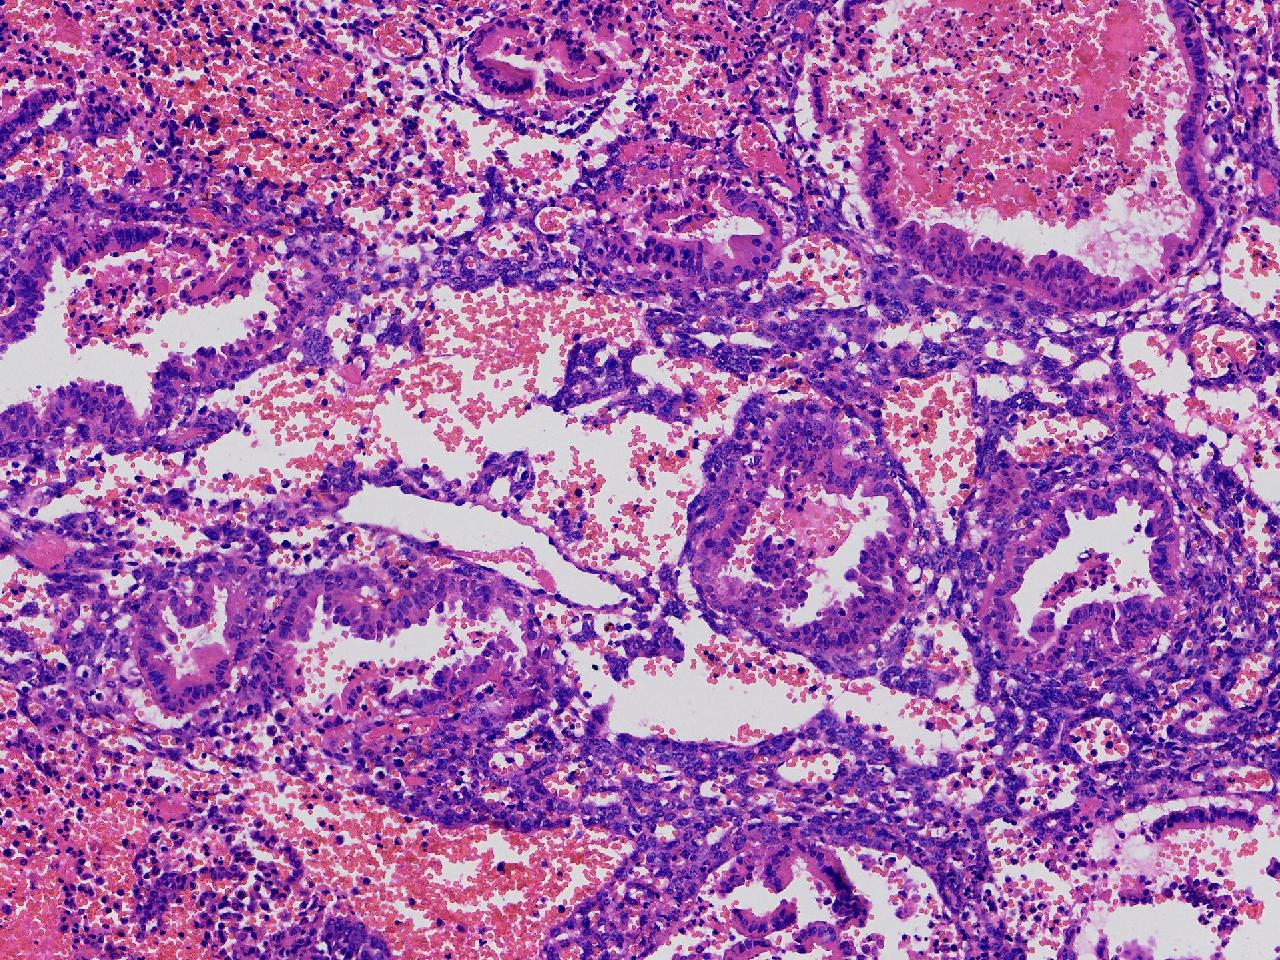

性别

女

年龄

45岁

临床诊断

阴道不规则出血20余天,

一般病史

彩超示:宫腔内见约41X11毫米的不均质回声区。宫腔镜示:宫腔形态正常,内膜粉红,不规则增厚。

标本名称

子宫内膜

大体所见

灰粉色不整形软组织多块,1.5X1X0.6厘米。

分泌反应子宫内膜,伴有出血。

晚泌期及月经早期改变,局部呈啫酸性乳头状化生改变。